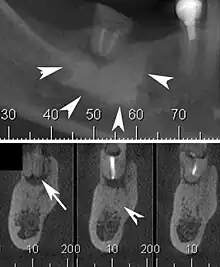

Cone beam CT scan presenting a diffuse hyperdense lesion in the apex of a mandibular molar (arrowhead, top) adjacent to an inflammatory periapical lesion (arrow, bottom).[1]